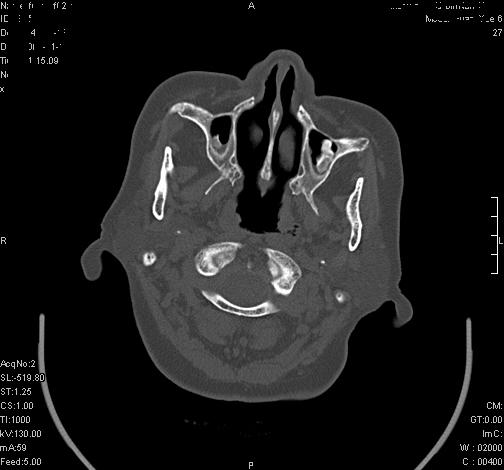

上次发的片子,不够细微。误导了大家,请大家再重新看一下,思路会更清晰。

双上颌窦高密度,其内见水样密度.考虑双上颌窦骨瘤伴上颌窦炎.

双上颌窦高密度,左侧病灶下部与左上颌窦底部骨质相延续,支持双上颌窦骨瘤

双侧上颌窦上部黏膜明显增厚、窦腔缩小,偏后侧窦壁骨质毛糙、模糊,窦腔内见条块状钙化。结合双侧鼻甲黏膜明显增厚,以及临床症状,

考虑:双侧上颌窦霉菌性鼻窦炎

双侧上颌窦密度增高,粘膜增厚,内见条片状钙化,窦壁无增生与破坏征象,双侧鼻甲粘膜肥厚.

意见:双侧霉菌性上颌窦炎.

温习:真菌性鼻旁窦ct特征 1)非侵袭性病变者可涉及到鼻腔和鼻窦,多为单侧,上颌窦最多见.2)ct示窦腔内软组织增生影,可呈息肉状,+c可强化3)增生软组织影内可见散在斑片状或沙砾状钙化区,此为其典型特点,4)

非侵袭性病变可见窦壁骨质增生,破坏少见;侵袭性病变可见窦壁骨质破坏.